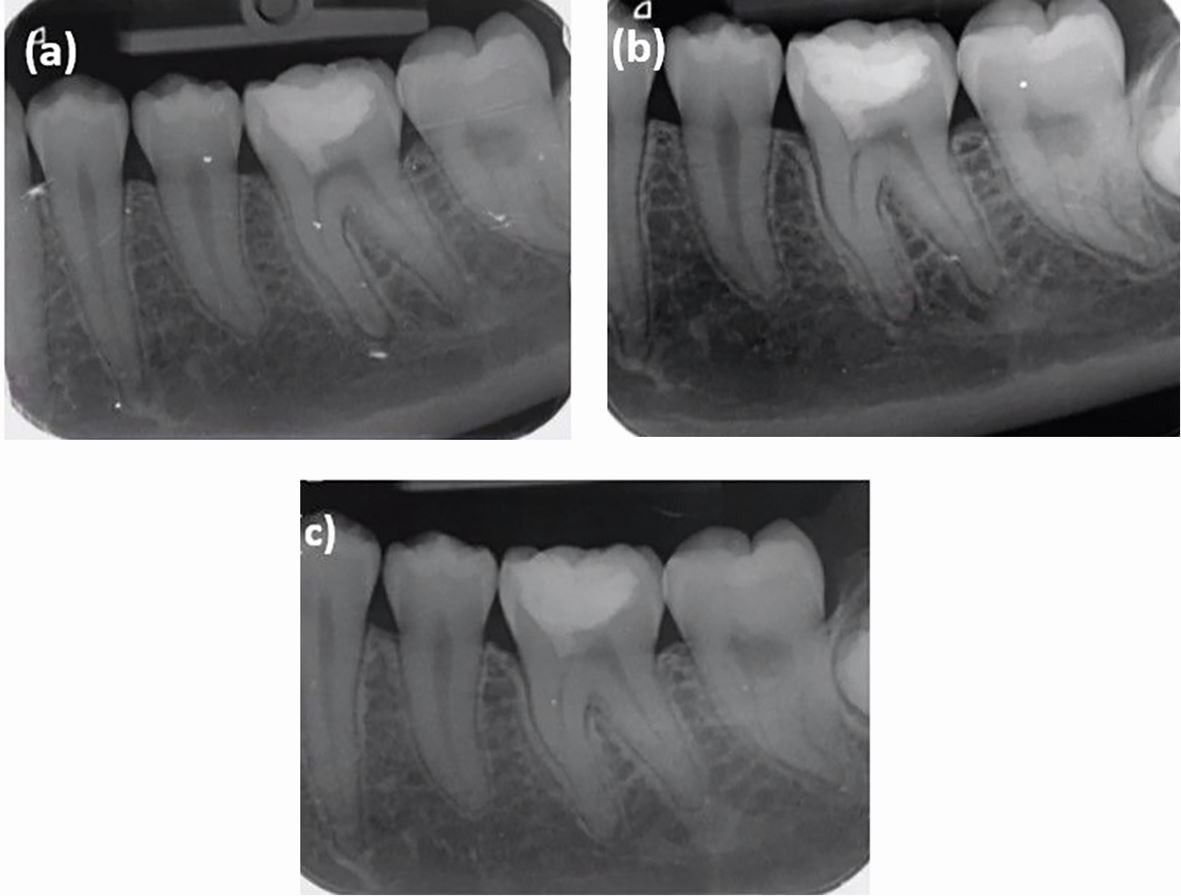

Post-operative radiographs. a) At baseline. b) At six months review. c) At two years and two months review